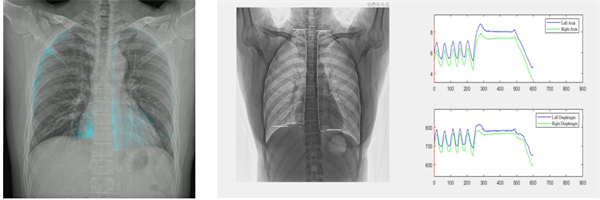

值得一提的是,安健科技目前已经在移动动态DR上实现肺功能成像技术,包括正式上市的肺通气分析以及在科研的肺血流灌注成像,这种基于动态成像的高级图像处理技术,能够提供更为深入的功能性分析,帮助诊断各种复杂的肺部疾病和其他慢性疾病。